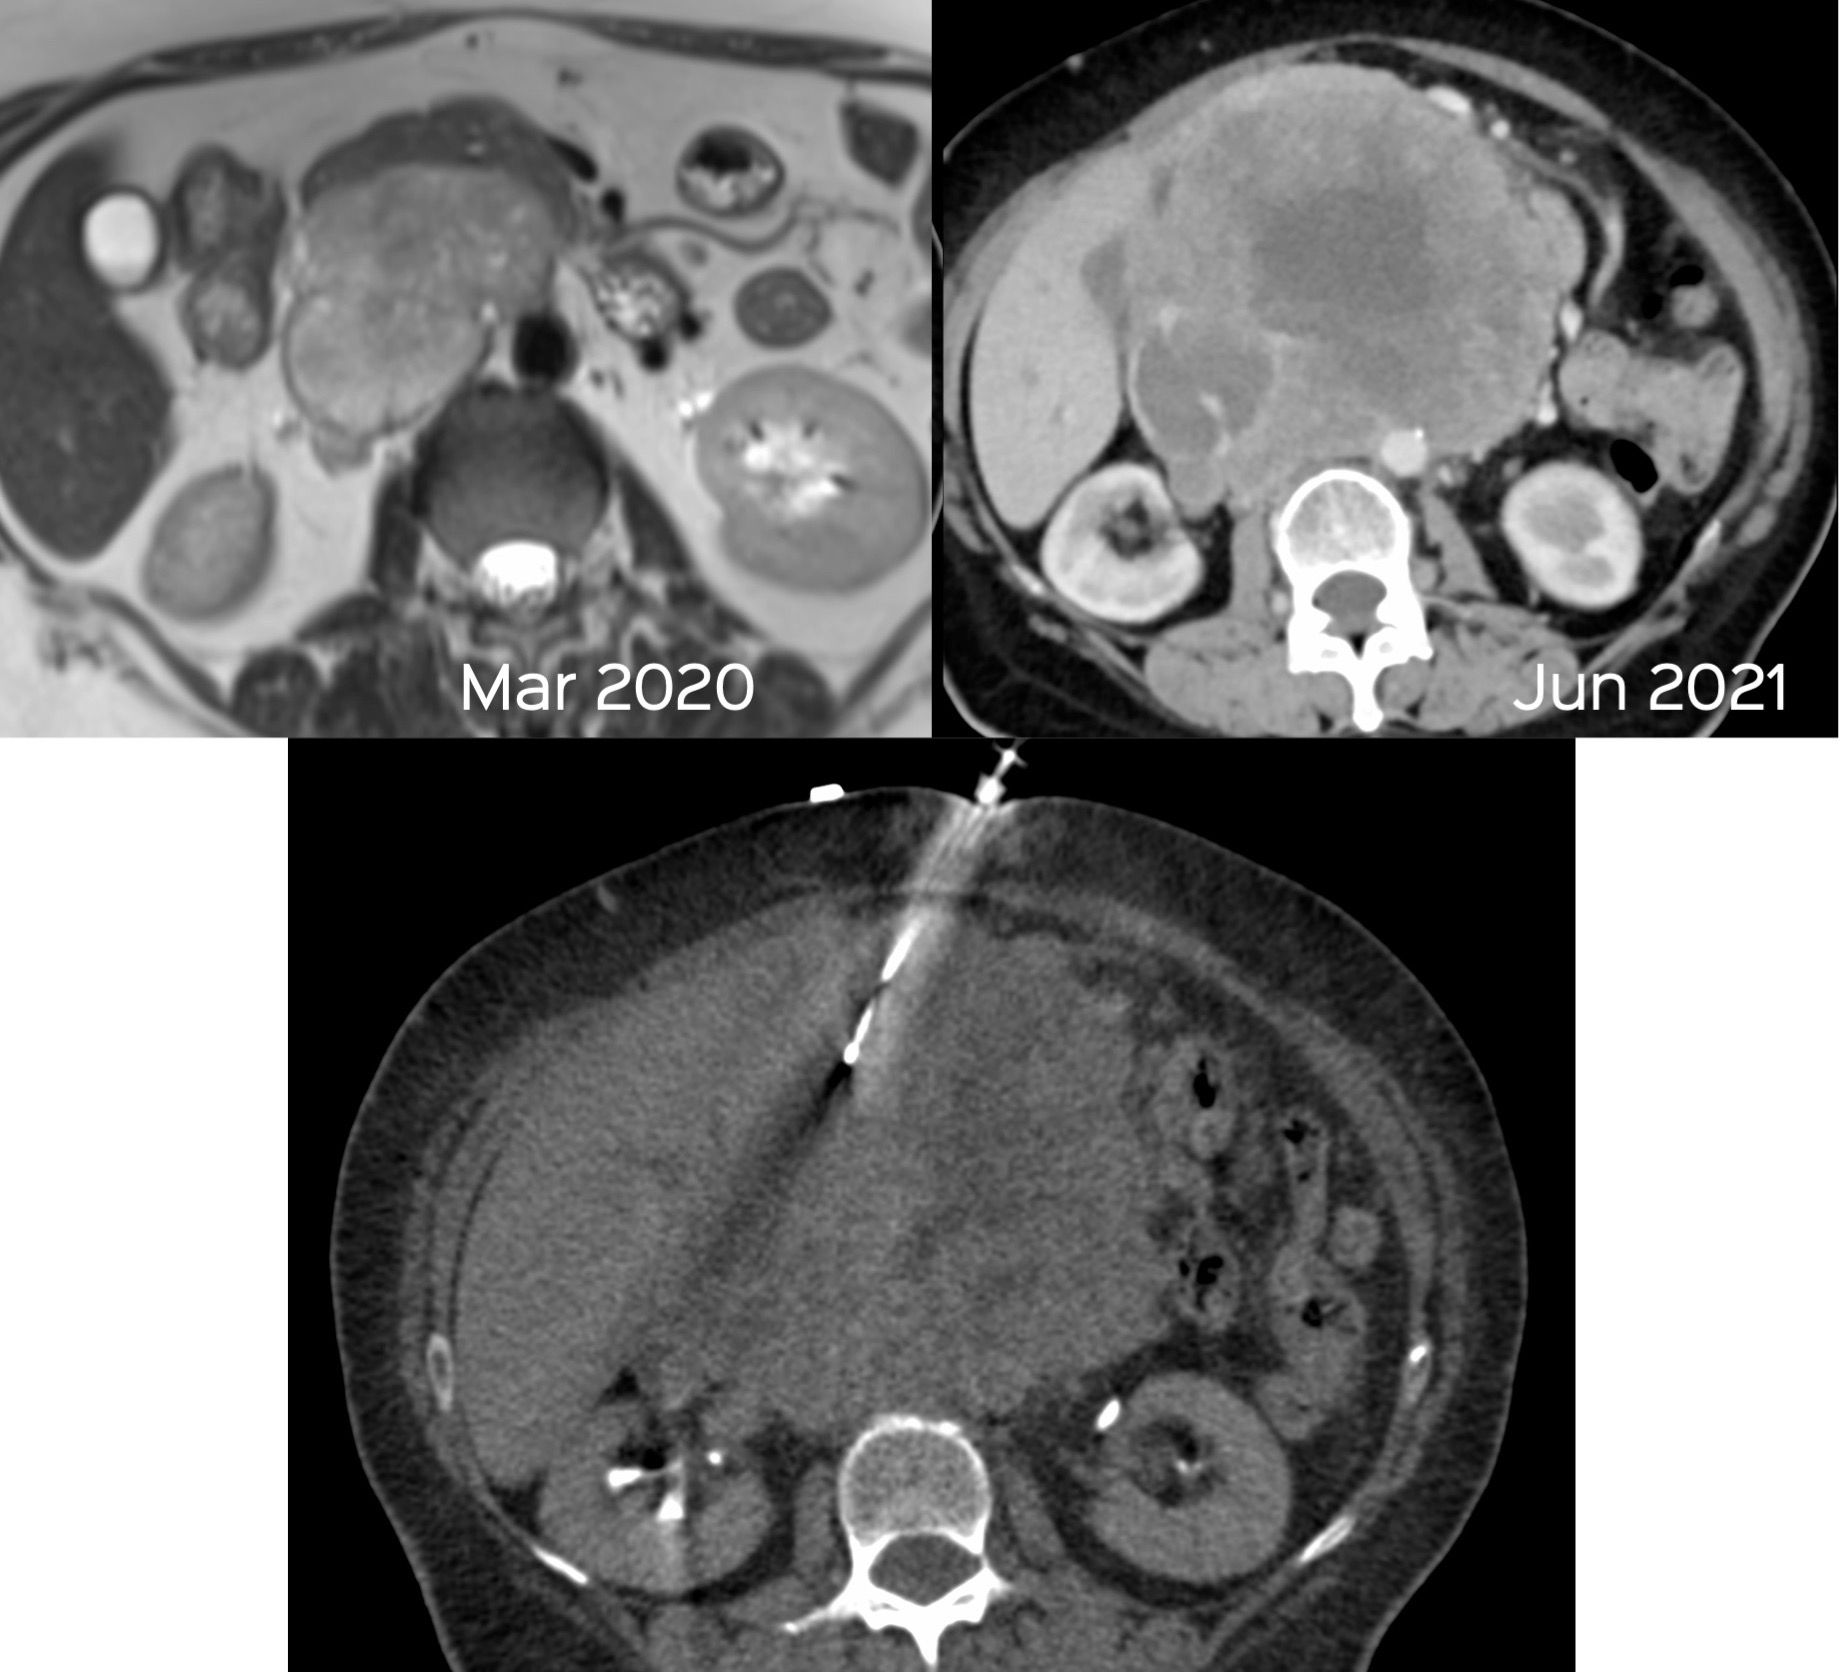

Case 42: Complex Retroperitoneal Mass with Intra-Procedural Intravenous Contrast

Bhavin Jankharia - 17 June 2021